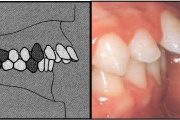

Vali sind huvitav pilt ja me näitame sellega seotud haigust ja sümptomeid